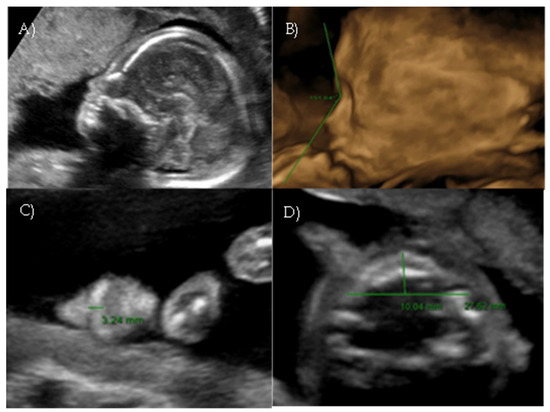

Targeted ultrasound at our center confirmed a flat profile suggestive of Binder-type maxillonasal dysplasia with a nasal-frontal angle of 150,72° (cut-off: <143°), flattening of the curvature of the maxillary alveolar processes (Width: 27 mm, cut-off at 21 weeks: 23.1 mm), short columella, and absent nasolabial philtrum (Figure 5A–D). The remaining fetal anatomy appeared normal.

A targeted anomaly scan at our fetal medicine unit revealed a flat and dysmorphic fetal facial profile with verticalization of the nasal bone, increased NFA, and short columella, suggestive of BP. An associated feature was polyhydramnios. The ultrasound findings were suggestive of Binder-type maxillonasal dysplasia (Nasal-frontal angle: 146.32°, cut-off: <143°) such as the flattening of the curvature of the maxillary alveolar processes (Width: 26.53 mm, cut-off at 22 weeks: 23.9 mm) (Figure 6A–D).

The routine anomaly scan was performed at our center at 20 weeks. A standard second-trimester ultrasound, following ISUOG guidelines 2022 [12], included visualization of the fetal facial profile in the midsagittal plane. The suspicion of an abnormal fetal profile was raised. Since a suspected craniofacial anomaly was present, a more detailed evaluation using axial, sagittal, and coronal planes was performed to assess the defect thoroughly by a fetal medicine expert. It revealed an isolated flat fetal facial profile suggestive of Binder-type maxillonasal dysplasia: the nasal-frontal angle measured 151.84° (cut-off <143°) and the maxillary width measured 27.62 mm (cut-off at 20 weeks: 22.4 mm) (Figure 7A–D).

Figure 5. Case 5. (A) Flat fetal profile with verticalization of the nasal bone. (B) Nasal-frontal angle: 150.72°. (C) Absent nasolabial philtrum. (D) Flattening of the curvature of the maxillary alveolar processes. Width: 27 mm.

Figure 6. Case 6. (A) Flat fetal profile with verticalization of the nasal bone. (B) Nasal-frontal angle: 146.32°. (C) Absent nasolabial philtrum. (D) Flattening of the curvature of the maxillary alveolar processes. Width: 26.53 mm.

Figure 7. Case 7. (A) Flat fetal profile. (B) Nasal-frontal angle: 151.84°. (C) Absent nasolabial philtrum. (D) Maxillary width: 27.62 mm.